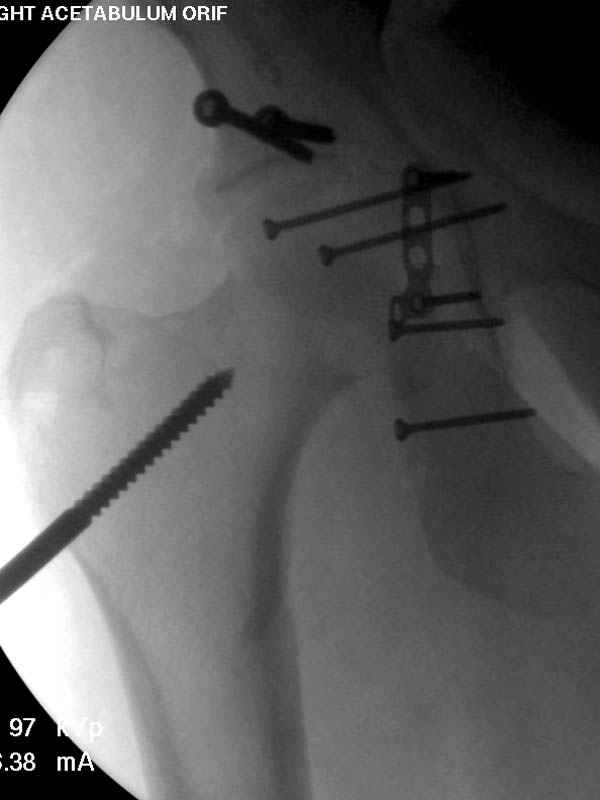

Латеральное положение облегчает проведение тракции через вертел, за 5 мм стержень за вертел (грузом через тракционное приспособление), на обычном рентгенопрозрачном операционном столе, а для положения на животе, наверное, Judet Table более приемлем, потому что там имеется латеральное тракционное устроиство.

Там множество обычных 2.7 мм шурупов, потом идет фиксация основными пластинами.

Снимки здесь....